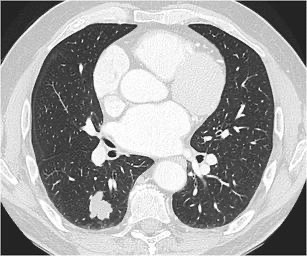

2396. Учитывая представленные на томографическом срезе данные и локализацию первичного железистого рака в паренхиме лёгкого у пациента, состоящего на диспансерном учёте по поводу хронической обструктивной болезни лёгких с объёмом форсированного выдоха за 1 секунду 60% от должного и стабильной стенакардии напряжения функциональный класс ii, целесообразно выполнение видеоторакоскопической